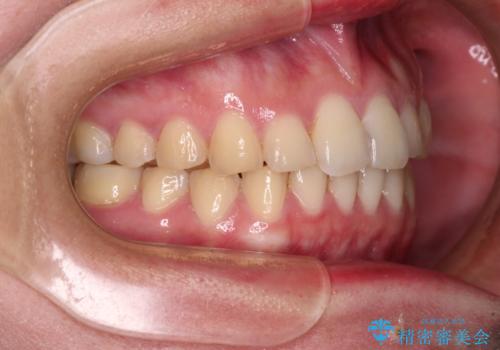

- 食いしばりが気になっていたとのことで来院された患者様です。

当初は睡眠時のマウスピースのみの製作をご希望でしたが、矯正治療の提案をしたところ、インビザラインにて矯正治療を行うこととなりました。

矯正治療中に食いしばりがより強くなることがあるため、半年に1回のペースでボツリヌストキシンによる咬合力緩和を並行して行うこととしました。

咬合力の緩和と食いしばりがちな咬み合わせが改善され、顎の負担が大幅に軽減されました。